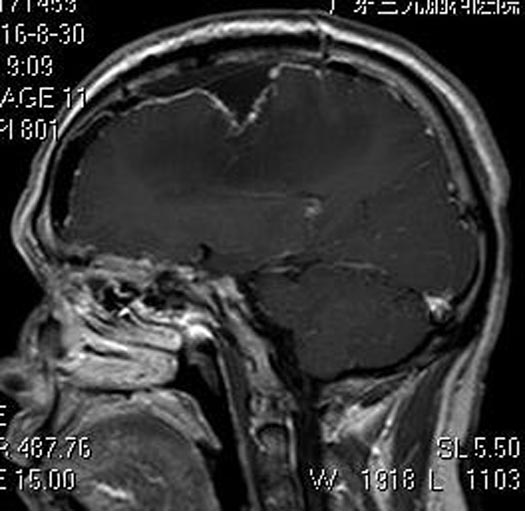

由综合神经外科鲁明主任主刀,在全麻下行右额部镰窦旁脑膜瘤切除术,显微镜下见肿瘤质软、血供丰富、边界尚清,予以肿瘤全切。术后王先生头痛及左侧肢体乏力明显好转。病理结果提示:脑膜皮细胞型脑膜瘤(WHO Ⅰ级)。

▲手术后